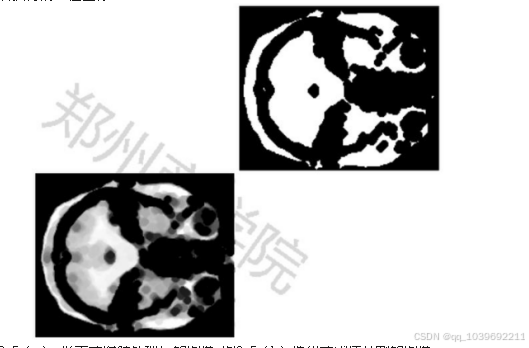

在程序中,首先读入预处理后的灰度图像,通过while循环语句获得最佳的阈值。[18]在获得最佳的阈值参数

后,通过函数im2bw对图像进行分割。[19]程序运行后,输出结果如图3-5所示。3-5(b)是通过迭代方法获得最佳阈

值后获得的二值图像。[20]

图3-5(a) 形态学腐蚀处理后的图像 图3-5(b)迭代式阈值分割的图像

经过迭代式阈值分割法处理后,MRI图像中的鸽脑部分已经趋于清晰,人眼可见呈现一团连通部分。本文采用连

通域标记法,采用MATLAB软件中的算法,提取图像中最大或最小部分,经过一次或多次操作,将图中的鸽脑部分提

取出来。MATLAB程序运行后,输出结果如图3-6所示。

图3-6(a) 形态学腐蚀处理后的图像 图3-6(b)迭代式阈值分割的图像